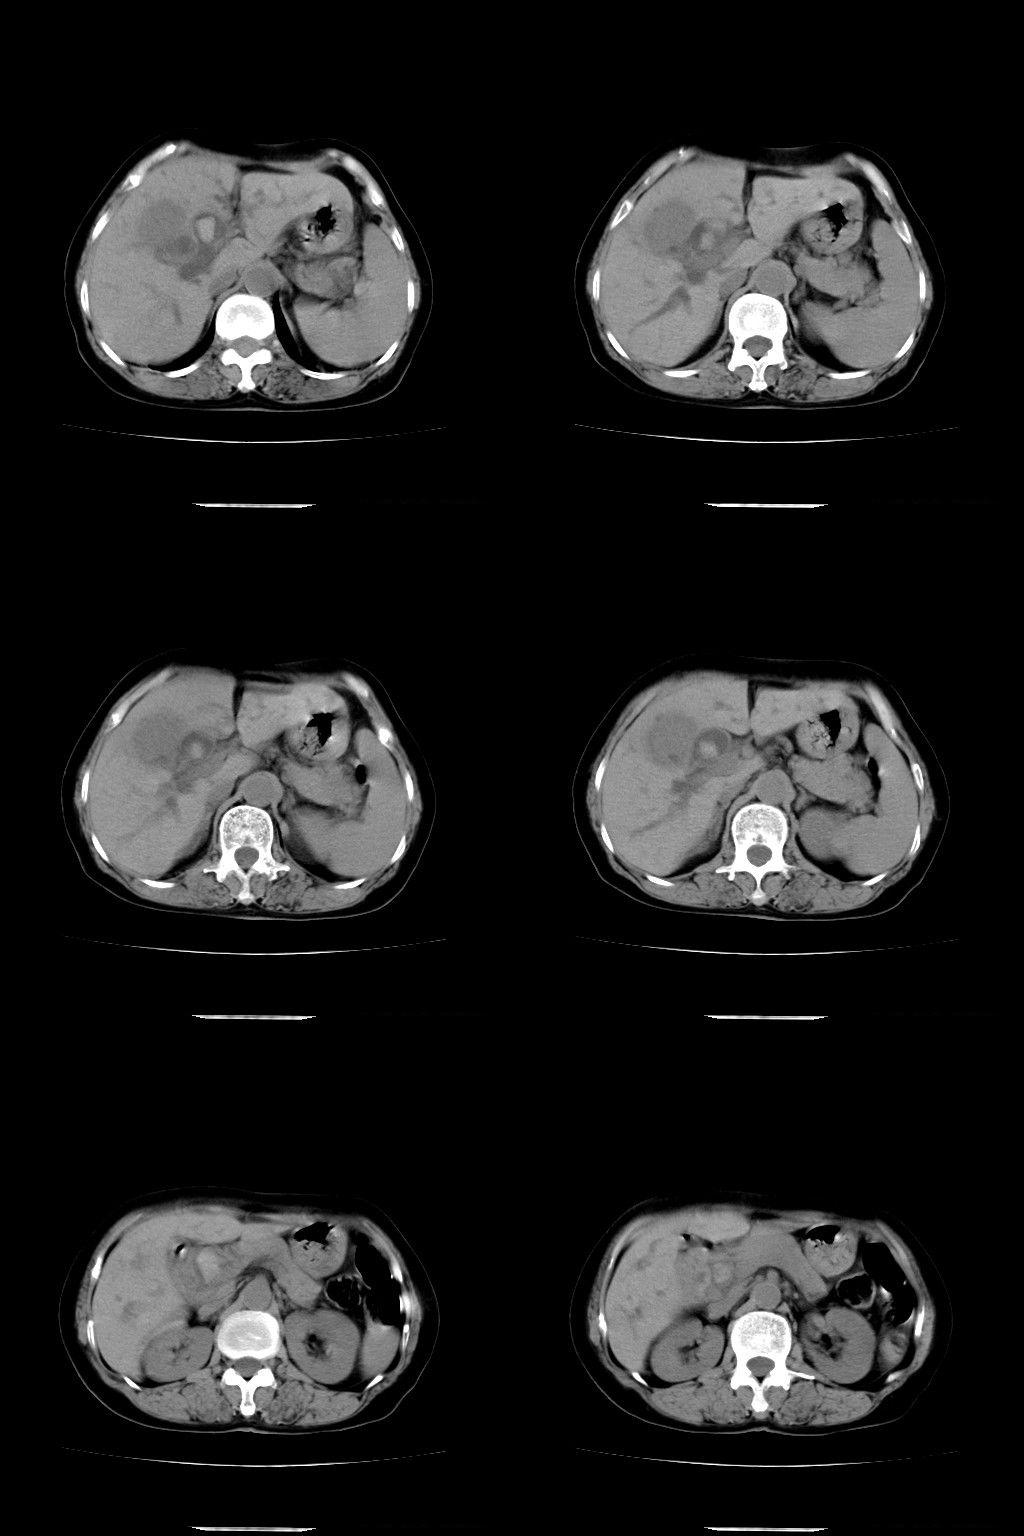

以下是引用余辉在2009-1-22 8:49:00的发言:[br]平扫肝内胆管扩张,右肝前叶球形低密度影,边缘较清楚,胆囊壁增厚,内可见较大高密度影,胆总管内亦可见高密度影,胰头区结构欠清。[br]增强动脉期见右肝前叶球形变灶明显增强,边缘见环状低密度区。胆囊见高密度影无增强,胆总管明显扩张,内见块状高密度影,周围环以低密度区,边界清楚。[br]静脉期见右肝前叶病灶持续增强,密度较动脉期增高。[br]考虑1胆囊及胆总管结石伴梗阻性胆系扩张,胆囊胆管炎。[br] 2右肝前叶占位性病变,强化规律符合胆管细胞癌,建议结合其他检查协诊